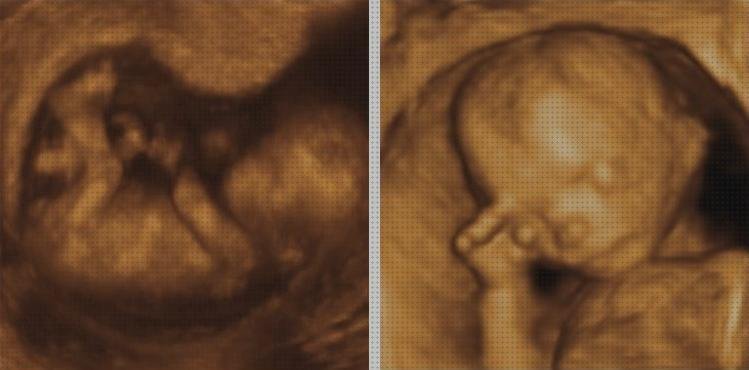

Vídeo sobre ecografías aparell sondas

Hemos buscado un vídeo referente a Cómo manejar la sonda ecográfica en Ecografía Obstétrica que te facilitará aun más a la hora de comprar ecografías aparell sonda médicas.